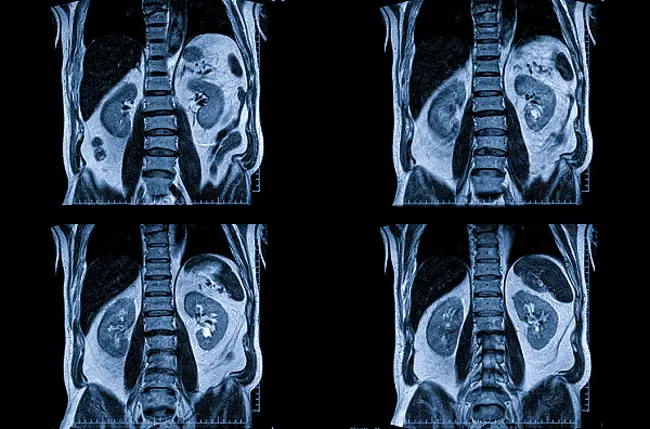

Что показывает МРТ почек? Этот метод хорошо визуализирует мягкие ткани, паренхиму, нервы, сосуды, а также подкожно-жировую и висцеральную клетчатку. При использовании контрастного вещества исследование кровеносной системы проходит гораздо более детально. Результаты сканирования позволяют выявить следующие патологии:

- опухоли почек;

- кистозные образования;

- деформации в почках и мочеточниках;

- туберкулез;

- гидронефроз;

- пиелонефрит;

- плохое кровоснабжение почек (инфаркт);

- гематомы;

- опущение почек;

- нефролитиаз;

- паразитарные повреждения.

МРТ с контрастированием может точно определить размеры и границы опухолей, оценить сосуды и кровообращение. Если целью исследования являются камни в почках, более эффективным будет использование компьютерной томографии.

На снимках четко просматриваются мочевой и желчный пузырь, надпочечники. Магнитно-резонансная томография помогает выявить патологические изменения в забрюшинном пространстве и оценить состояние соседних мягких тканей и сосудов.

На МР-томограммах в аксиальной проекции органы имеют нормальную форму и положение. Структура изображений неоднородная, что обусловлено наличием в субкапсулярных отделах нижней трети левой почки простой кисты размером 4 мм, заполненной серозным содержимым. В передних отделах нижней трети правой почки отмечается объемное образование округлой формы с четкими контурами, интенсивно накапливающее контрастное вещество в позднюю артериальную фазу сканирования, что создает яркий МР-сигнал.

МРТ почек позволяет выявить даже незначительные изменения их структуры, что облегчает диагностику заболеваний на ранних стадиях. Сканирование может проводиться в трех проекциях, при необходимости можно получить и трехмерное изображение исследуемой области.

На снимке МРТ видно наличие кисты почки.

3D-модель помогает уточнить расположение анатомических структур и оценить степень поражения паренхимы.

При планировании хирургического вмешательства объем и особенности операции зависят от данных, полученных в результате МРТ почек. Томограммы позволяют визуализировать размеры и расположение патологического очага, состояние окружающих тканей, а также особенности кровоснабжения области исследования.